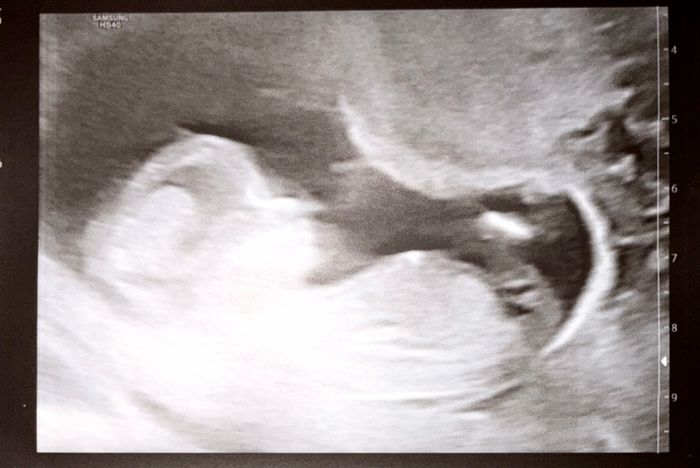

Hola chicas, que me diríais..? Es una eco donde se aprecian los genitales 15+4Método Ramzi 4